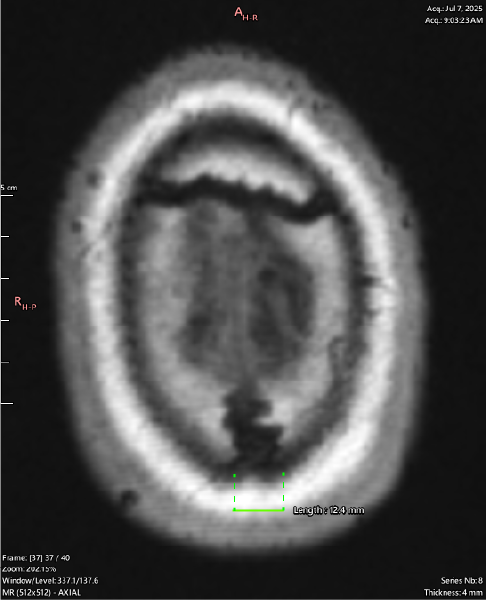

<- (Length 12.4mm)

T1 Coronal

T1 Axial

Again showing a 12.4mm outside margin for the Sagittal suture. This slice shows both cranial sutures (Sagittal + Coronal) are displaying the same hypointense tissue signal along the entirety of their visible length.

It also demonstrates that this osteolytic process is not confined to the sutures along, and has spread to the surrounding bone including the cortical layer (black rim around the white signaling marrow).

The fibrous tissue entity is also shown as invading the subcutaneous fat layer (white around the cortical bone), and the skin.

^ (Length 12.4mm) ^